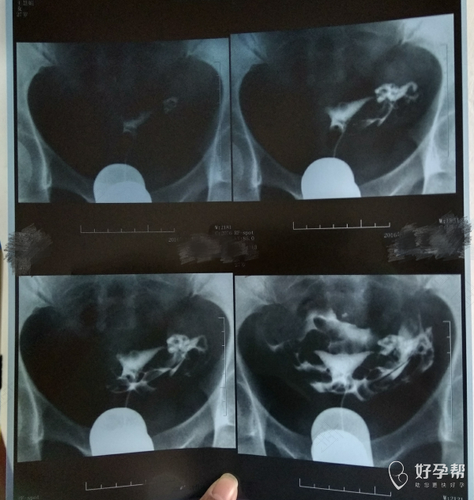

输卵管造影会比较疼,因为输卵管造影是将一种造影剂打入到输卵管腔里面,过程跟通水一样,但是在造影的同时,还要做X线拍片检查,然后看输卵管是不是有造影剂弥散,这样的造影剂有没有弥散在盆腔中,从而来判断输卵管是否通畅。由于造影的时间要比通水的时间长,所以相对来说,造影会更加痛。